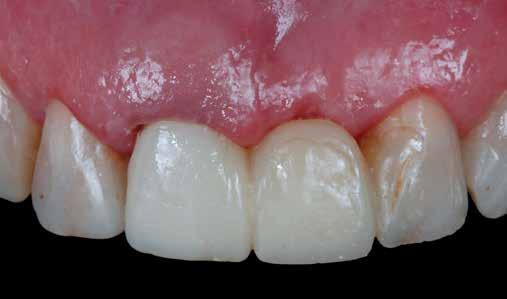

A rendelésünkön jelentkező 40 éves nőbeteg a mosolyának esztétikai megjelenésén szeretett volna javítani (1. ábra)

A vizsgálat során a jobb felső első kisőrlőfog (1,4) és a bal felső első kisőrlőfog (2.4), valamint a köztük elhelyezkedő fogak kifejezett mértékű kopását észleltük (14-24). Ezen felül a felső metszőfogak (1.2–2.2) élei egyenetlen lefutással rendelkeztek, és a jobb felső nagymetszőfog (11) – amelyet korábban gyökérkezeltek és kompozit töméssel láttak el –jelentős színbeli eltérést mutatott. Az 1.4-es és 2.4-es fo-

A belső fogfehérítés utáni állapot.

gak között mért tasakmélység mértéke sehol sem haladta meg a 3 mm-t. A páciens számára belső fogfehérítést, ínyplasztikát és kerámia héjak készítését javasoltuk. A páciens a felajánlott kezelési tervet elfogadta. Első lépésként az 1.1es fog belső fogfehérítését terveztük, mivel a későbbiekben ezt a fogat is kerámia héjjal akartuk ellátni.

A páciens elégedett volt a végleges restaurátumok színével, formájával és méretével. A kezelés végeredménye kielégítette az esztétikai elvárásait (9. ábra). A frissen átadott restaurátumok épségének megőrzése érdekében a páciens számára éjszakai fogvédősínt készítettünk. A páciensünk a négyéves kontrollvizsgálat során is nagyon elégedett volt a kezelés eredményével. A korábban meglévő fekete háromszögek eltűnésének különösképpen örült (9. és 10. ábrák)

9. ábra. A beavatkozás után, valamint a 4 évvel később látható állapot. (A): Egy héttel a ragasztás után készült felvétel. (B): A négyéves kontroll alkalmával készült felvétel.